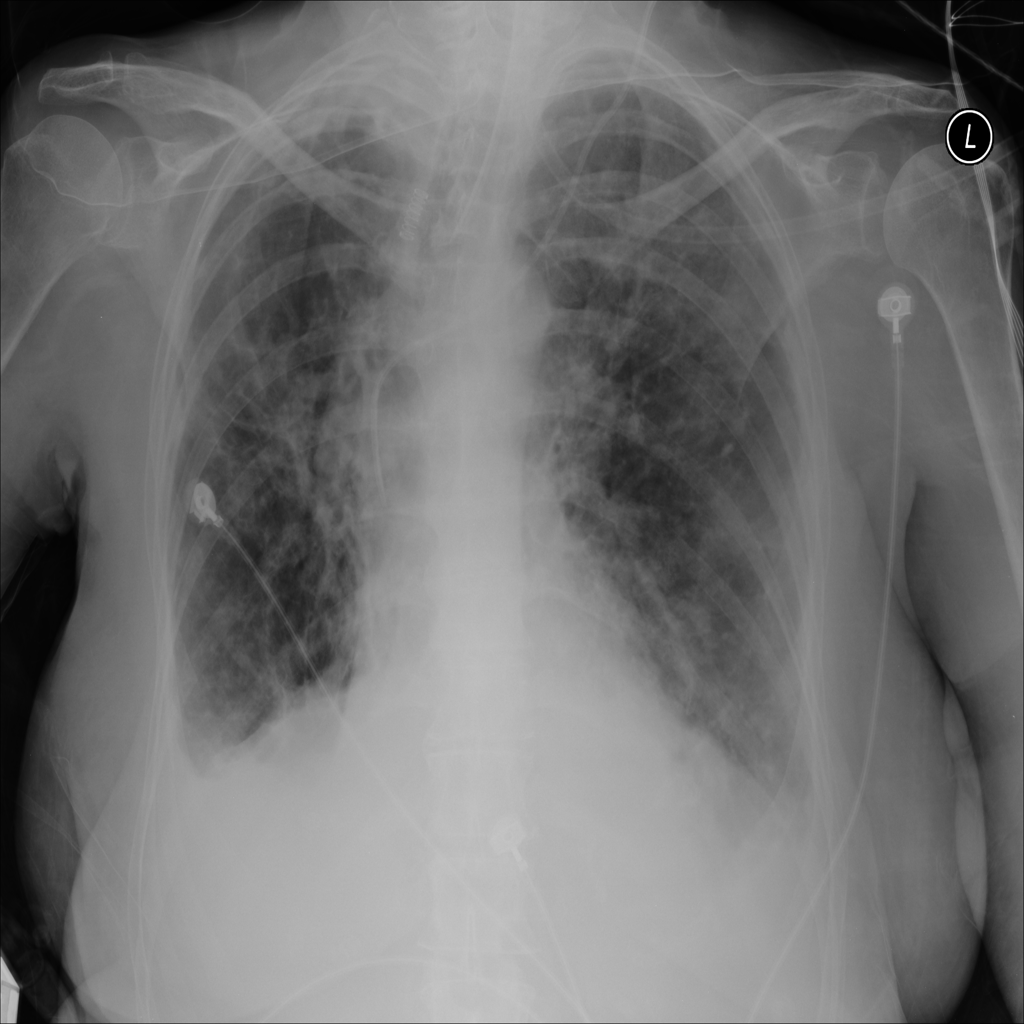

PAT-E066 · IMG-010Fibrosis

PAT-E066 · IMG-010

PA